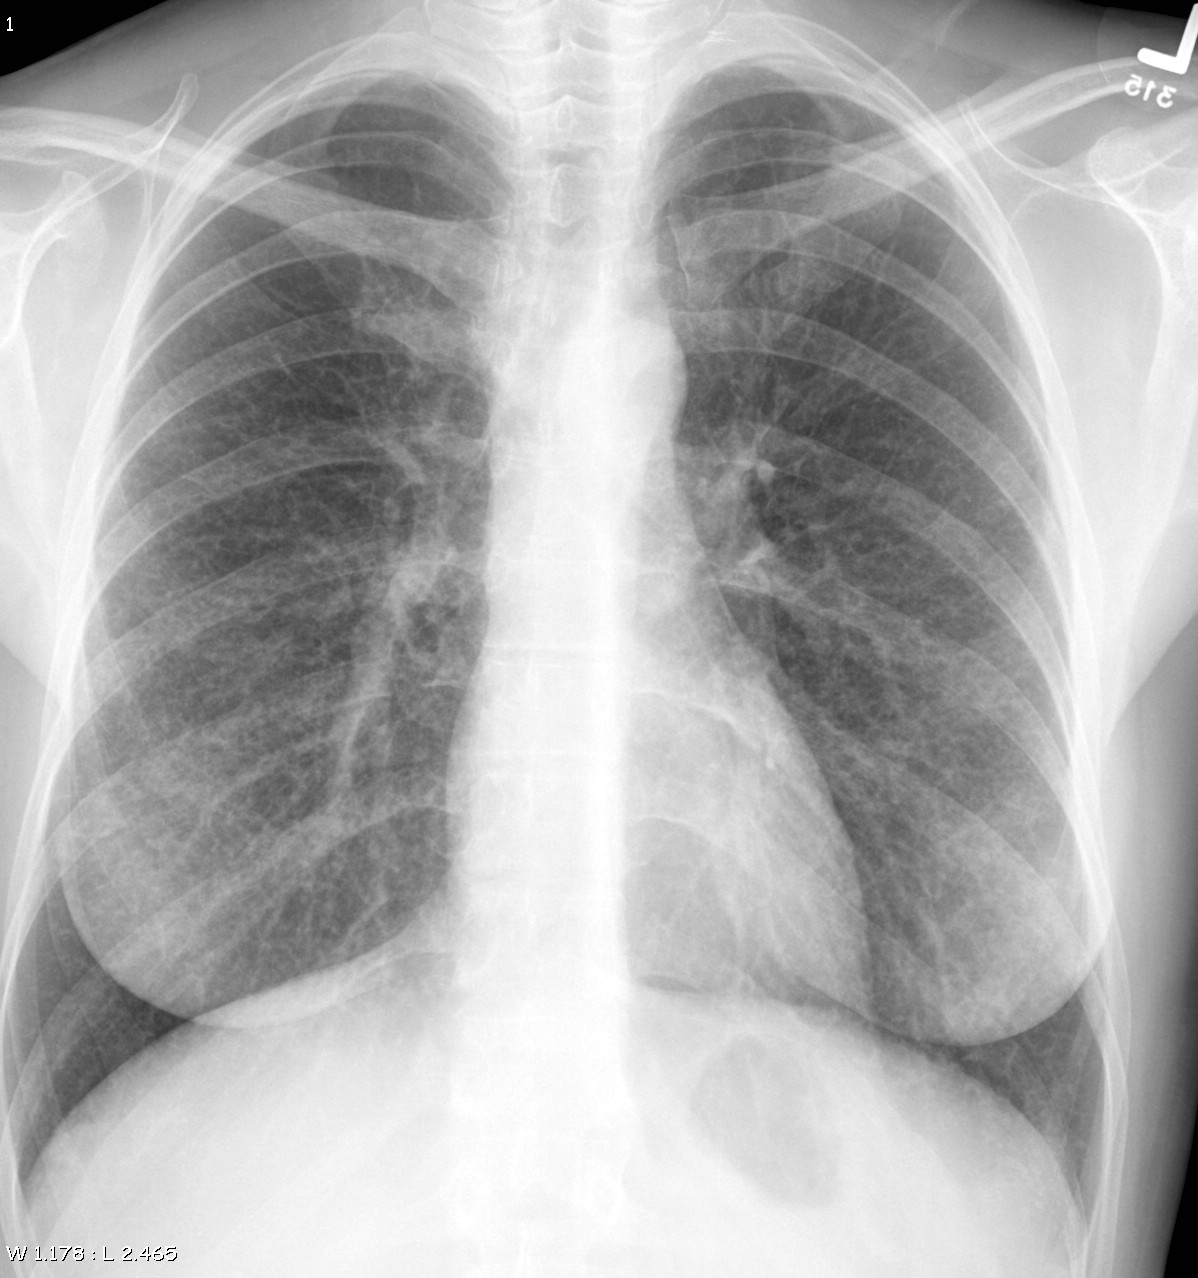

Gallery Sarcoid Sarcoid Case 21

Sarcoid

Case 21